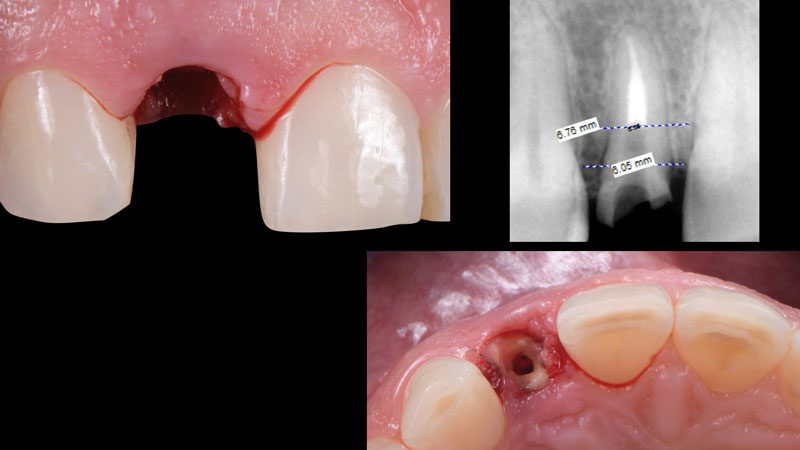

Bài viết dưới đây sẽ dẫn chúng ta đến với 1 ca lâm sàng cắm Implant tức thì răng cửa bên hàm trên. Implant được chỉ định vì thân răng bị gãy quá sâu dưới nướu, cấu trúc răng còn lại không đủ để thực hiện phục hồi.

Hình 1. Hình ảnh răng cửa bên hàm trên bị gãy sâu dưới nướu, chú ý khoảng cách chiều ngang (gần – xa) đo được trên phim quanh chóp.

Hình 2. Nhổ răng sang chấn tối thiểu bằng hệ thống Benex để bảo vệ xương và mô mềm xung quanh.

Hệ thống nhổ răng không sang chấn Benex.